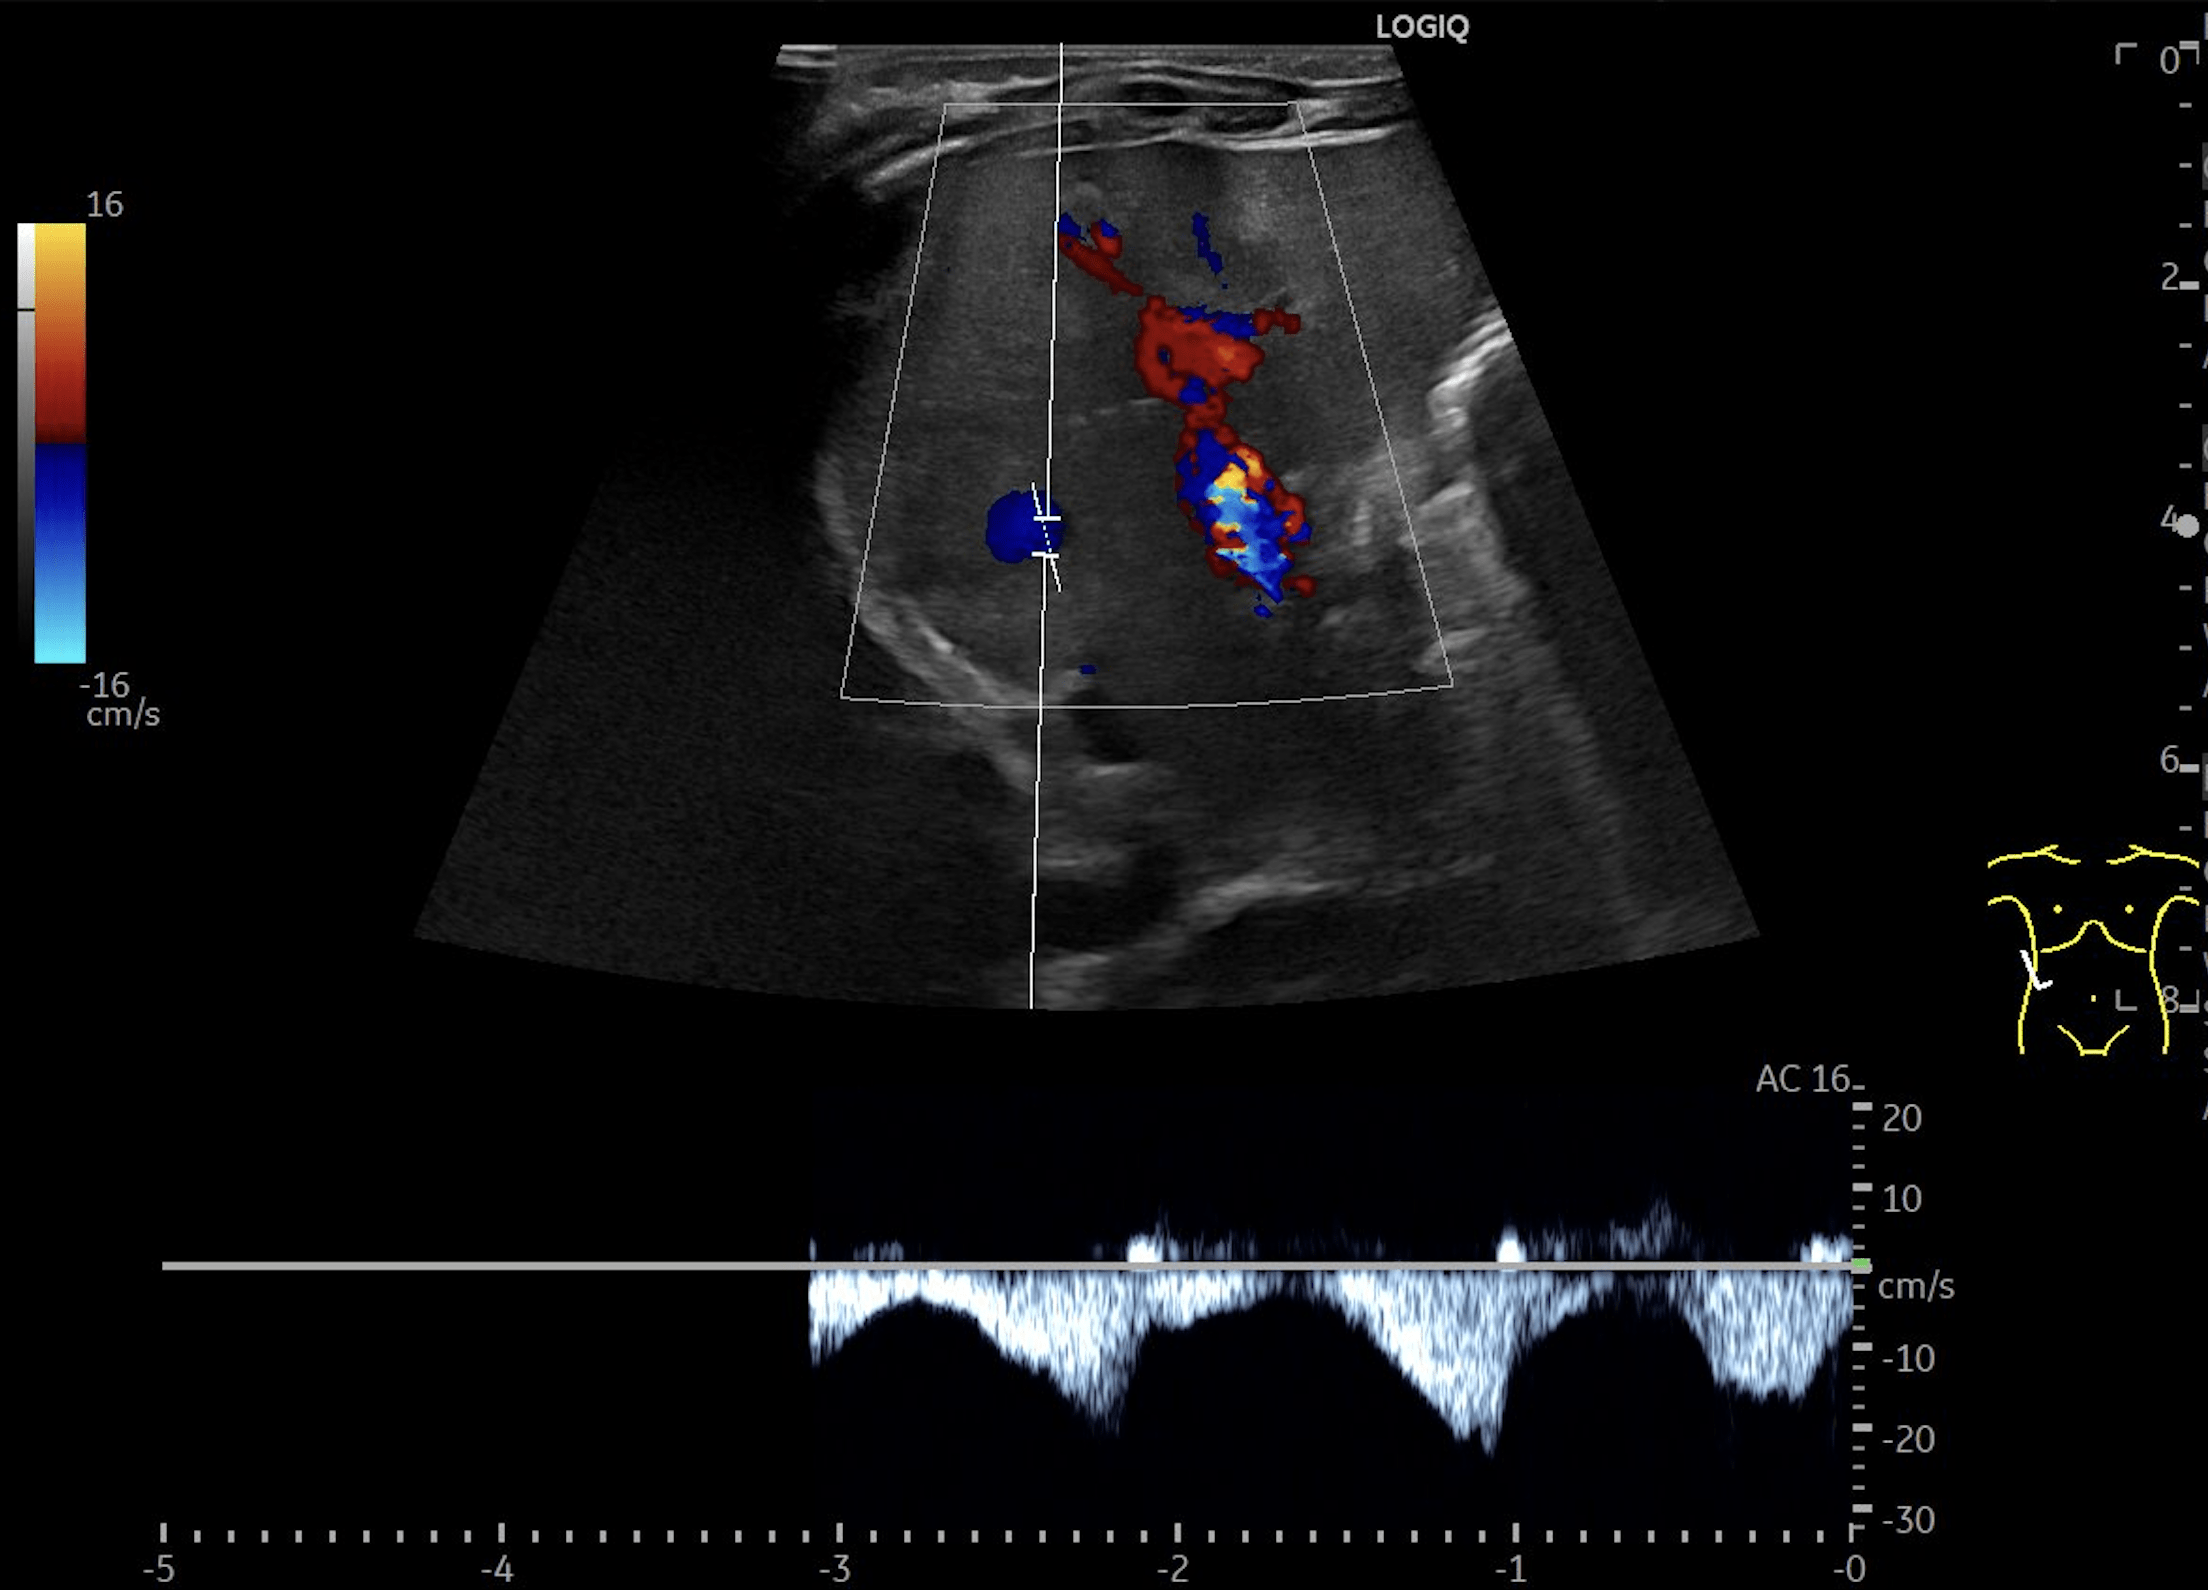

B: Doppler image of capillary hemangioma located ventrally in the right hepatic lobe, demonstrating large, tortuous vessels suggestive of possible arteriovenous shunting.

Multiple hepatic lesions were identified on ultrasound (A). Some lesions appeared as typical, well-defined hyperechoic cavernous hemangiomas (2), while others demonstrated large, tortuous vessels. Additional lesions showed a hyperechoic rim with a hypoechoic center and internal Doppler flow, consistent with capillary hemangiomas (2). In some HH (B), arteriovenous shunting was suspected. However, Triplex Doppler examination demonstrated normal hepatoportal flow in the portal vein (C) with flow velocities below 40 cm/s – within the normal range for the age – as well as a normal triphasic flow pattern in the hepatic veins (D).

In the present case, multiple hemangiomas – both cavernous and capillary subtypes - were detected in both liver and spleen. Some of the hepatic lesions demonstrated features suggestive of arteriovenous shunting.

• Comprehensive hemodynamic assessment with Doppler and Triplex Ultrasound: Hepatic hemangiomas and the hepatic vasculature should be evaluated using Doppler and Triplex ultrasound to assess for possible arteriovenous shunting and hemodynamic consequences.